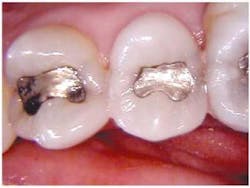

Recurrent caries is difficult to diagnose around an existing amalgam using radiographs. An occlusal DIFOTI image (Fig. 3) will demonstrate recurrent caries around an existing dental restoration.

Interproximal vertical fractures emanating from existing amalgam restorations are easily seen and demonstrated to the patient. This case not only demonstrates deep vertical cracks but also decay.

In Fig. 4 (below) teeth numbers 3, 4, and 5 are shown. It would be difficult to demonstrate to the patient the problems that are present.